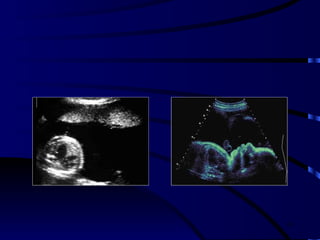

Hidrosefali & Kongenital

Toksoplazma